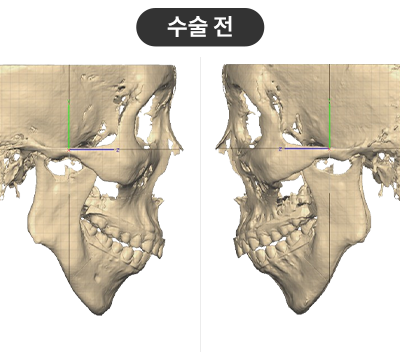

무턱이 심한 환자로, 턱을 앞으로 빼서

정상 범위 내로 개선을 희망

무턱이 심한 환자로, 턱을 앞으로 빼서

정상 범위 내로 개선을 희망

STEP 01

3D플랜에 따라 최적의 위치로 상-하악을 위치시킴

STEP 02

무턱 교정을 위해 하악을 앞으로 이동시켜 적정한 교합을 맞춤

STEP 03

플랜을 기반으로 제작된 Wafer를 장착하고 뼈를 고정

수술결과

무턱 개선 : 턱 끝 기준 14mm 전진